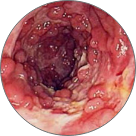

Тромбоза на хемороидалните јазли со локална некроза на ткивото

Венозна стаза во патолошки изменети проширени вени

Крвавење од потслизестите крвни садови, што доведува до некроза на ткивото и анемија

Ректален карцином